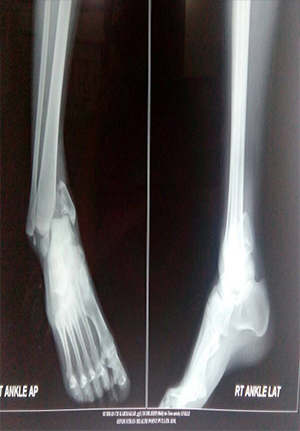

Ankle Fracture fixation

Fracture disocation Ankle treated by ORIF